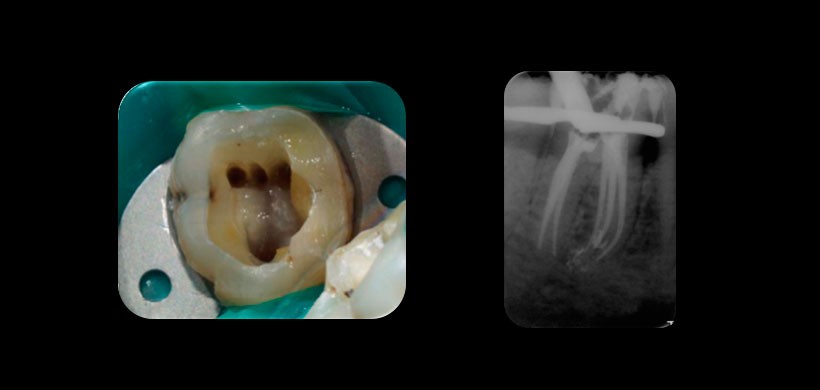

Figura 1: Presencia de conducto medio mesial, que se unen junto al conducto mesiovestibular y al mesiolingual terminando en un foramen unico.

Figura 2: Presencia de conducto medio mesial, totalmente independiente a los conductos mesiovestibular y al mesiolingual, llegando incluso a tener un propio foramen apical.